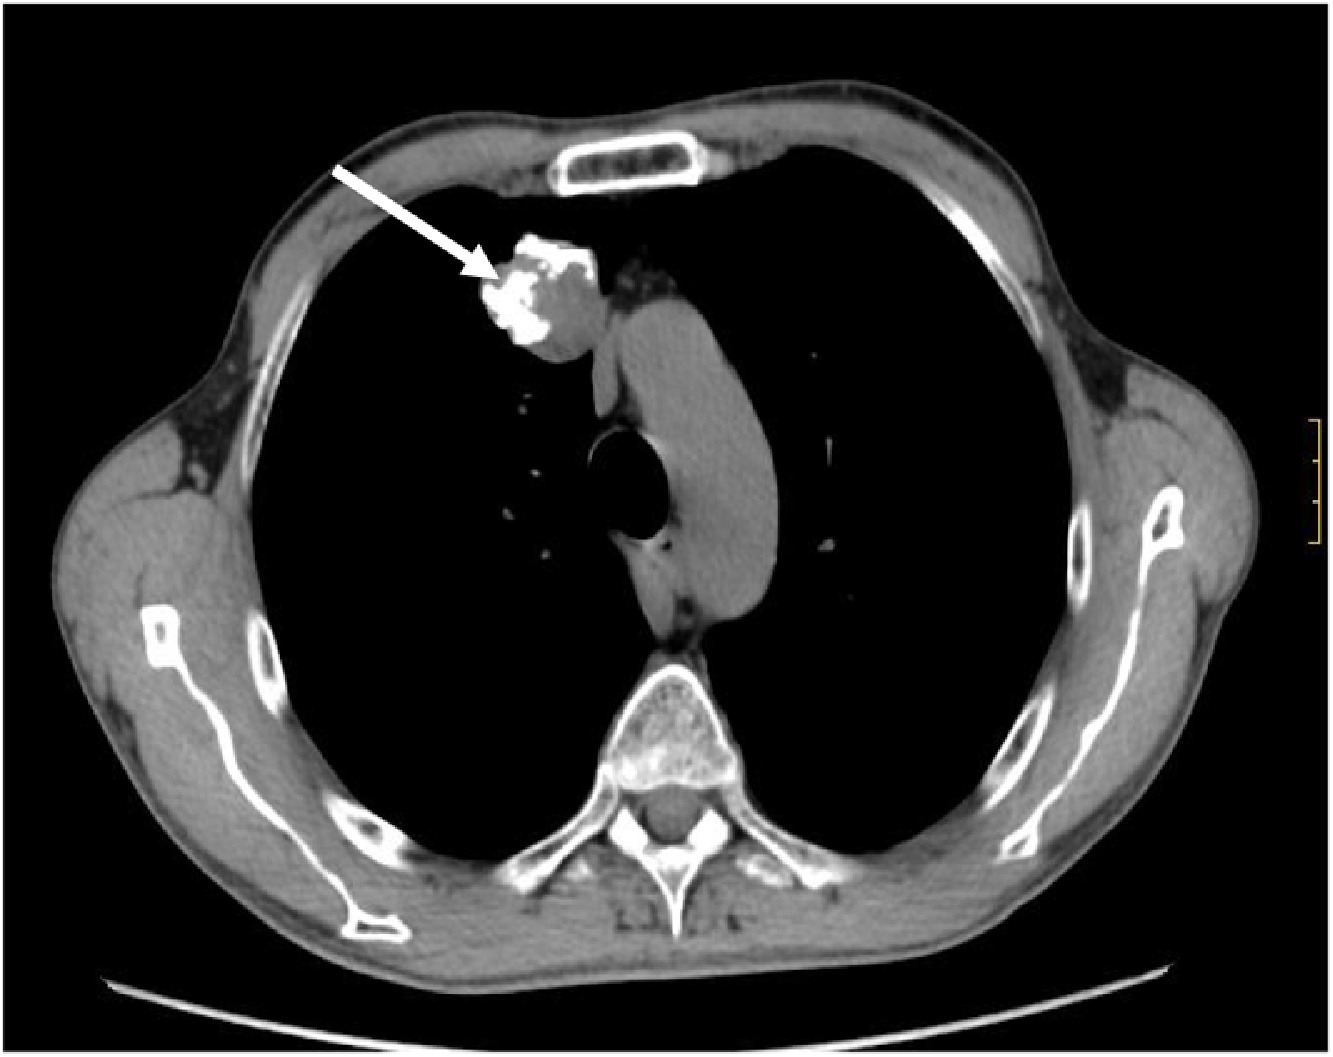

Hamartoma - The most common benign lung nodule is called a hamartoma. Hamartomas are clumps of normal connective tissue (cartilage), fat, and muscle that measure less than 2 inches2. They show up on imaging as round, white spots in your lungs. Hamartomas account for about 75 percent of all benign lung tumors. Nearly 80 percent of this nodule type occurs in your lung’s connective tissues, while the remaining 20 percent show up inside your bronchial tubes. More men than women develop hamartomas by a 2:1 margin3.

- Higher calcium content

- Smooth, even shape

- Even color